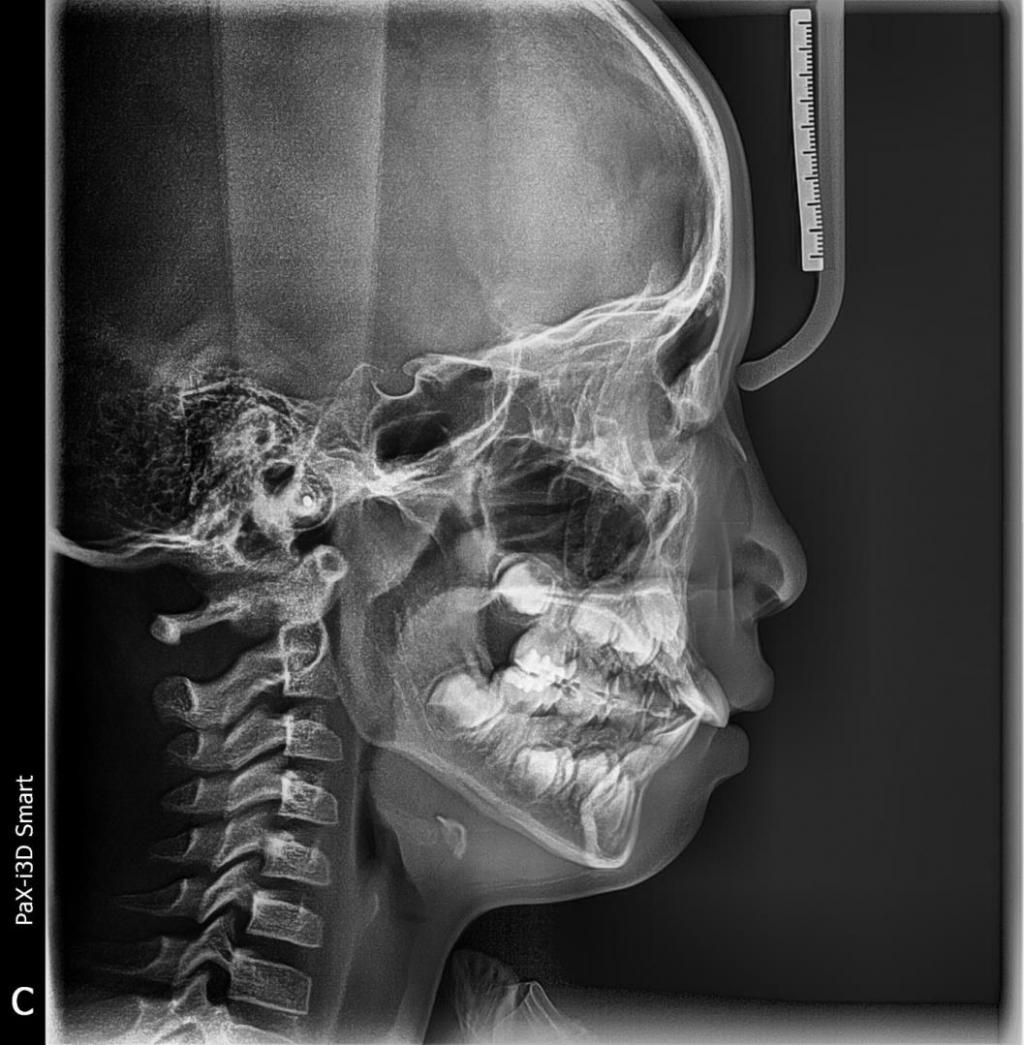

현재 저는 외국에 거주중이라 교정치과를 결정하기가 더 힘이 드네요..ㅠㅠ 초등3학년 아이의 앞니가 돌출되어있는 상태입니다.

정확히는 앞니 네개가 돌출이라고 봐도 되겠네요.

앞니의 영향인지 아랫니도 바깥으로 살짝 나왔다고 하네요.

앞니의 크기가 큰 상태이고 추후 영구치가 가지런히 나올 공간이 부족하다고 해요.

턱 모양이 무턱에 가깝고 의식해서 입술에 힘을주지 않으면 입도 다물어지지 않습니다.

어금니 두개랑 앞니 네개만 브라켓부착해서 자가결찰을 사용해도 악궁확장효과와 앞니의 돌출이 어느정도는 해소가 되는게 맞을까요?